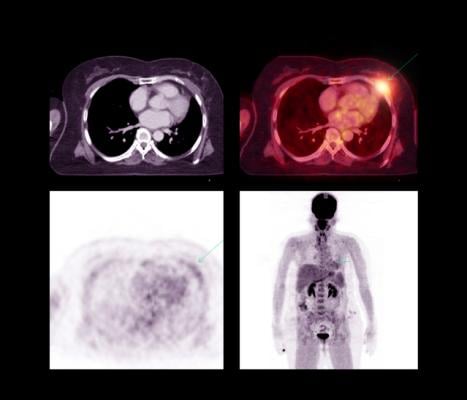

April 11, 2022 — Radiation to the heart during treatment for locally advanced lung cancer is associated with an increased risk of major adverse cardiac events within the first two years following treatment. The higher the cardiac dose exposure, the higher the risk of a cardiac event.

A team at the University of Michigan Health Rogel Cancer Center, in partnership with the statewide Michigan Radiation Oncology Quality Consortium (MROQC) lung cancer collaborative, co-led by Shruti Jolly, M.D., and Peter Paximadis, M.D., of Spectrum Health Lakeland in St. Joseph, Michigan, found that raising awareness about the risk of radiation exposure to the heart and standardizing cardiac exposure limits reduced the average dose to the heart by 15% and reduced the number of patients receiving the highest heart doses by half without minimizing tumor treatment or increasing dosage to other at-risk organs in the chest.